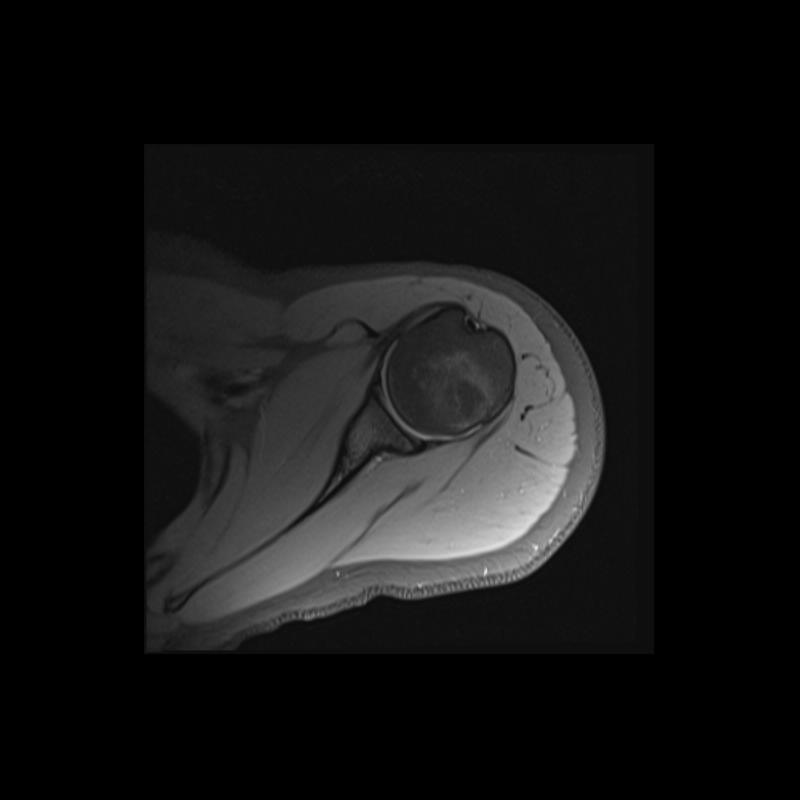

Shoulder MRI Anatomy